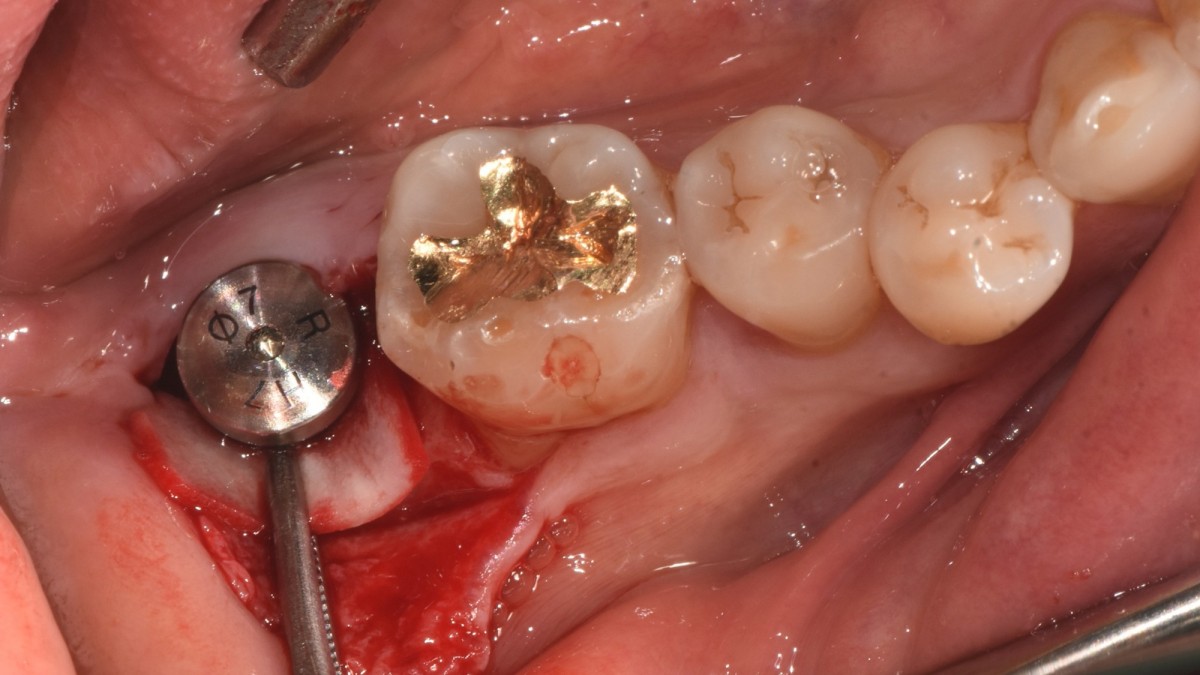

Single implant (staged) Arum NB1, f/u

A 47-year-old male patient had a crown with an ill-fitting margin and crack-tooth syndrome in the lower 2nd molar. No systemic issue.